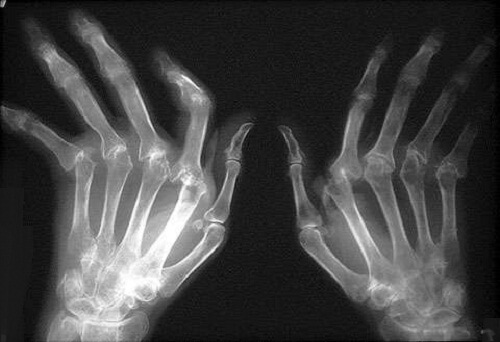

関節リウマチは、関節の軟骨部分を守る膜の炎症によって起きる慢性的な病気です。骨が炎症を起こすと、骨への損害及び侵食が引き起こされます。これは、関節の軟骨部分のみに損害を与える関節症とは違います。関節リウマチは、特に40歳以上の女性に大きな痛みを引き起こします。この記事では、どのように関節リウマチを治療するかを紹介します。

1番分かりやすい症状は関節部分の炎症と腫れであり、これは大きな痛みを引き起こします。関節リウマチの影響を受けやすいのは、手首、肘、肩、指、足の指、お尻、足首と膝です。関節リウマチの患者は、朝起きた時にこわばりを感じる事が多いようです。

また、肌(特に手や足の裏)や体内にこぶが出来る、慢性関節リウマチ小節が症状として現れる事があります。この炎症は、関節リウマチが進行するにつれて関節の変形へと移行します。